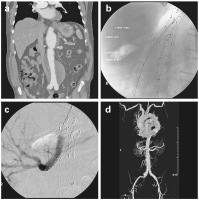

Fenestrierte Endoprothese

Abbildung 1a-d: Implantation einer fenestrierten Endoprothese. (a): CT-Rekonstruktion des thorakoabdominellen Aneurysmas; (b): partiell abgesetzte Endoprothese, Sondierung der Nierenarterie und der A. mesenterica superior, Einlegen von Schleusen; (c): nach voller Entfaltung der Endoprothese Absetzen der Überbrückungs-Stent-Grafts; (d): Abschlussangiographie.